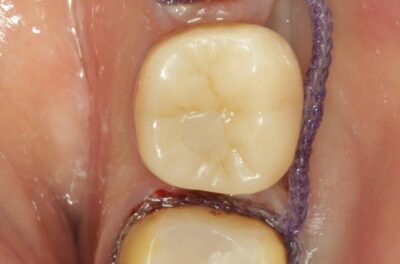

Протезирование коронками из диоксида циркония, после эндодонтического лечения — Исламов Л.А.(01.04.2026)